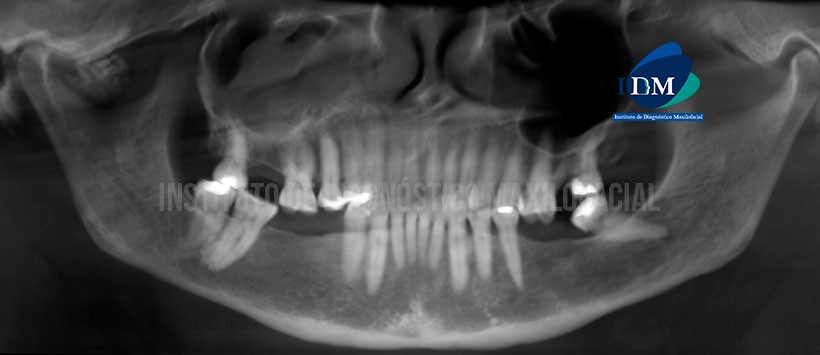

En la reconstrucción panorámica tomográfica (Figura 1) se observa presencia de múltiples imágenes hiperdensas en zona anterior del cóndilo mandibular derecho.

A la evaluación de la tomografía volumétrica (CBCT) cortes axiales (Figura 2), coronales (Figura 3), sagitales (Figura 4), sagitales y coronales de las ATMs (Figuras 5 y 6), se observa, en boca cerrada: presencia de múltiples imágenes hiperdensas de diversos tamaños y formas irregulares de densidad de hueso compacto y esponjoso, localizados a nivel anterior (por debajo de la eminencia articular), adyacente a la parte externa del cóndilo mandibular derecho y un cuerpo libre a nivel posterior del cóndilo, se extiende hacia la base craneal media (por debajo de la porción petrosa del hueso temporal), se aprecia aplanamiento y esclerosis subcondral del cóndilo mandibular derecho y disminución severa del espacio articular anterosuperior (compresión articular). En boca abierta: Trayectoria y desplazamiento bicondílea dentro de los parámetros normales, masas de cuerpos libres acompañan levemente el desplazamiento condilar derecho.